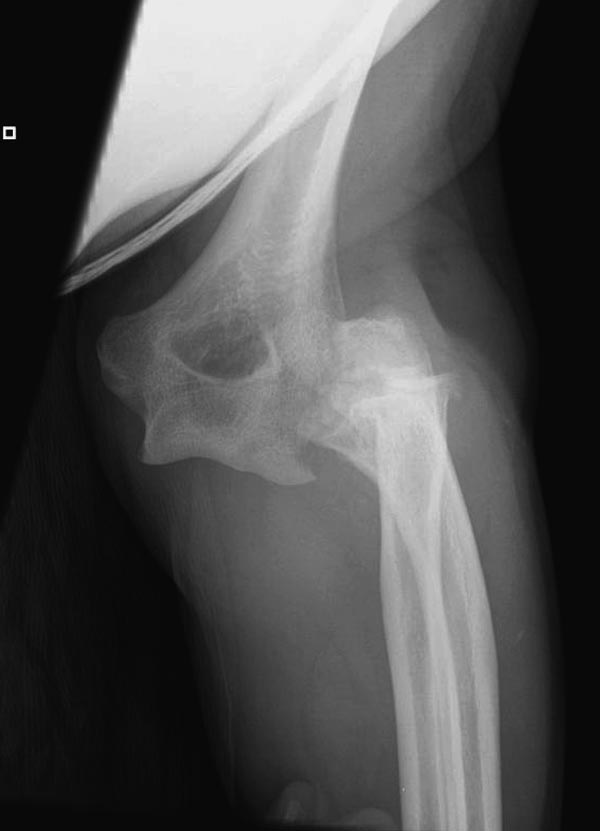

Один снимок всего? Может КТ-срезы какие-нибудь есть, R-снимки без гипса фас/профиль? По этому снимку вроде бы и нет вдавленного перелома. Суставная поверхность расколота - это да, но импрессии не увидел. Мы бы попытались сохранить головку.

Синтезировать, или вообще не трогать. А 3D картинки дают мало информации. Лучше представляйте срезы в 3-х плоскостях.

Для выработки показаний достаточным бывают стандартные снимки, но иногда требуется косая рентгенограмма по Coyle. И для подтверждения смещений и оценки внутрисуставных фрагментов рекомендуется КТ, а 3D снимки показывают только поверхность, т.е. получается общая картина. МРТ дает возможность оценить состоянии связок.

В первом случае перелом Монтеджи, где доперационно сделано оценка положения головки к остальным элементам под рентгеном. Учитывая правильность взаимотношении произведена фиксация только локтевого отростка, Второй случай, заменена на протез, и третий, кроме фиксации головки - реконструкция capitellum латерального мыщелка.